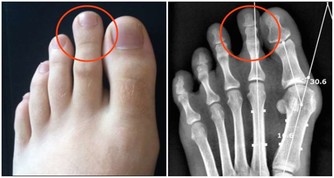

其二,牙疼也有可能引起牙周疾病。它是一種緩慢的破壞性疾病,患者如不及時接受治療,是有可能引起牙齒鬆動,甚至脫落,對日後的進食和咀嚼都造成不利的影響。